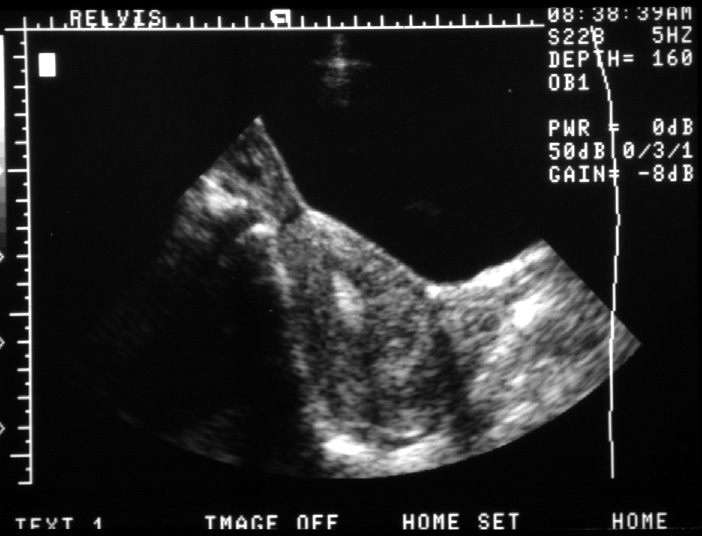

Note. This image is a lingitudinal scan through the bladder and the

uterus. The patient's head is to the viewer's left. The large

black area ventrally is the patient's bladder. The uterus is the

eggshaped echogenic structure immediately dorsal to the bladder.

Centrally within the uterus are several very bright echoes representing

the endometrial cavity.